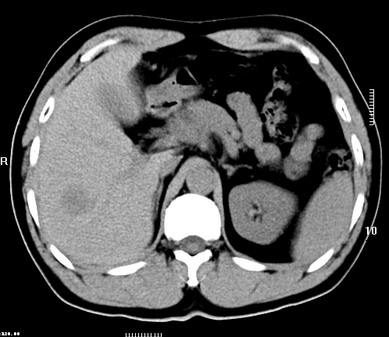

标题: CT19720:肝右叶血管瘤。肝左叶内侧段病灶考虑什么? [打印本页]

标题: CT19720:肝右叶血管瘤。肝左叶内侧段病灶考虑什么?

男,48岁,肝区不适月余,伴隐痛。

支持右叶血管瘤,左叶病灶考虑肝腺瘤。

1)不排除肝左叶肝癌。2)肝右叶血管瘤。

肝左叶炎性病变,肝癌待排。2)肝右叶血管瘤。

1.肝右叶血管瘤;2.肝左叶炎性假瘤?肝癌?建议穿刺活检.

右叶病灶典型,左叶病变慢性炎块

1、肝右叶血管瘤(典型)。

2、肝左叶病灶,强化不明显,疑炎性假瘤,建议结合临床并密切随访。

1、肝左叶炎性病变,肝癌待排。

2、肝右叶血管瘤。

肝左叶脓肿,肝癌待排。2)肝右叶血管瘤